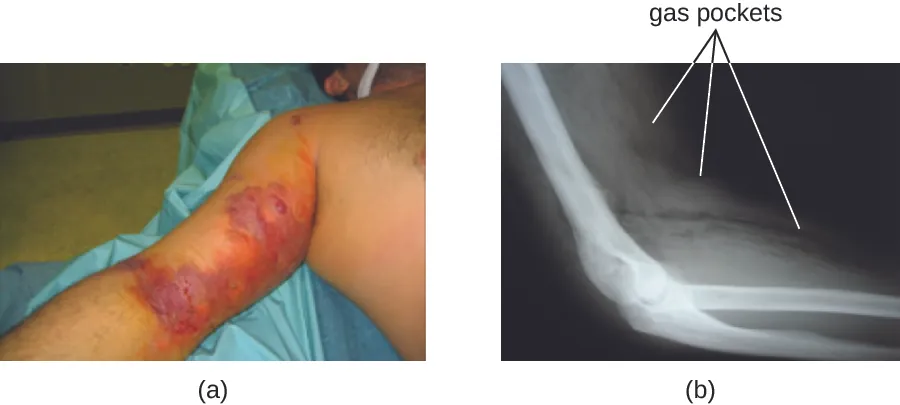

The resulting infection, called gas gangrene, is characterized by rapidly spreading myonecrosis (death of muscle tissue). The patient experiences a sudden onset of excruciating pain at the infection site and the rapid development of a foul-smelling wound containing gas bubbles and a thin, yellowish discharge tinged with a small amount of blood. As the infection progresses, edema and cutaneous blisters containing bluish-purple fluid form. The infected tissue becomes liquefied and begins sloughing off. The margin between necrotic and healthy tissue often advances several inches per hour even with antibiotic therapy. Septic shock and organ failure frequently accompany gas gangrene; when patients develop sepsis, the mortality rate is greater than 50%.

α-Toxin and theta (θ) toxin are the major virulence factors of C. perfringens implicated in gas gangrene. α-Toxin is a lipase responsible for breaking down cell membranes; it also causes the formation of thrombi (blood clots) in blood vessels, contributing to the spread of ischemia. θ-Toxin forms pores in the patient’s cell membranes, causing cell lysis. The gas associated with gas gangrene is produced by Clostridium’s fermentation of butyric acid, which produces hydrogen and carbon dioxide that are released as the bacteria multiply, forming pockets of gas in tissues (Figure 25.7).

a) Photo of an arm with large purple and red regions. B) X-ray of an arm showing white muscles and cloudy skin. A dark black band cuts through the skin.

Figure 25.7 (a) In this image of a patient with gas gangrene, note the bluish-purple discoloration around the bicep and the irregular margin of the discolored tissue indicating the spread of infection. (b) A radiograph of the arm shows a darkening in the tissue, which indicates the presence of gas. (credit a, b: modification of work by Aggelidakis J, Lasithiotakis K, Topalidou A, Koutroumpas J, Kouvidis G, and Katonis P)